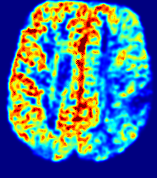

LesionRefer to captionRefer to captionRefer to captionRefer to captionRefer to captionRefer to caption𝐕rgbsubscript𝐕𝑟𝑔𝑏{\bf{V}}_{rgb}Refer to captionRefer to captionRefer to captionRefer to captionRefer to captionRefer to caption𝐕2subscriptnorm𝐕2{\|\bf{V}}\|_{2}Refer to captionRefer to captionRefer to captionRefer to captionRefer to captionRefer to captionRefer to caption3.53.53.52.82.82.82.12.12.11.41.41.40.70.70.70.00.00.0(mm/s)𝑚𝑚𝑠(mm/s)D𝐷DRefer to captionRefer to captionRefer to captionRefer to captionRefer to captionRefer to captionRefer to caption0.0200.0200.0200.0160.0160.0160.0120.0120.0120.0080.0080.0080.0040.0040.0040.0000.0000.000(mm2/s)𝑚superscript𝑚2𝑠(mm^{2}/s)Slice #1Slice #2Slice #3Slice #4Slice #5Slice #6

Figure 3: PIANO feature maps for one stroke patient, where the lesion is located in the left hemisphere. Top row: segmented stroke lesion region (white) on different slices, obtained from ISLES 2017. The corresponding slices for the PIANO feature maps are shown in the following rows.

For a better insight into an estimated velocity field 𝐕𝐕{\bf{V}} and diffusion field 𝐃𝐃{\bf{D}}, we compute the following maps: (1) 𝐕rgbsubscript𝐕𝑟𝑔𝑏{\bf{V}}_{rgb}: Color-coded orientation map of 𝐕=(Vx,Vy,Vz)T𝐕superscriptsuperscript𝑉𝑥superscript𝑉𝑦superscript𝑉𝑧𝑇{\bf{V}}=(V^{x},V^{y},V^{z})^{T}, obtained by normalizing 𝐕𝐕{\bf{V}} to unit length and mapping its 3 components to red, green, blue respectively; (2) 𝐕2subscriptnorm𝐕2\|{\bf{V}}\|_{2}: 222 norm of 𝐕𝐕{\bf{V}}; (3) D𝐷D: scalar field in Eq. 5.

Fig. 3 and Fig. 4 show the PIANO feature maps estimated from two ISLES 2017 patients: all are highly consistent with the lesion in both cases. Details of the blood flow trajectories are revealed in 𝐕rgbsubscript𝐕𝑟𝑔𝑏{\bf{V}}_{rgb} by the ridged patterns and the sharp changes of colors in the unaffected (right) hemisphere, while the flat patterns appearing within the lesion provide little directional information about the velocity and indicate low velocity magnitudes. Velocity magnitudes are more directly visualized via 𝐕2subscriptnorm𝐕2\|{\bf{V}}\|_{2}, from which one can easily locate the lesion where 𝐕2subscriptnorm𝐕2\|{\bf{V}}\|_{2} is low. D𝐷D also indicates lower diffusion values in the lesion, though with less contrast potentially due to the fact that it captures the accumulated effect of CA diffusion at the voxel-level.